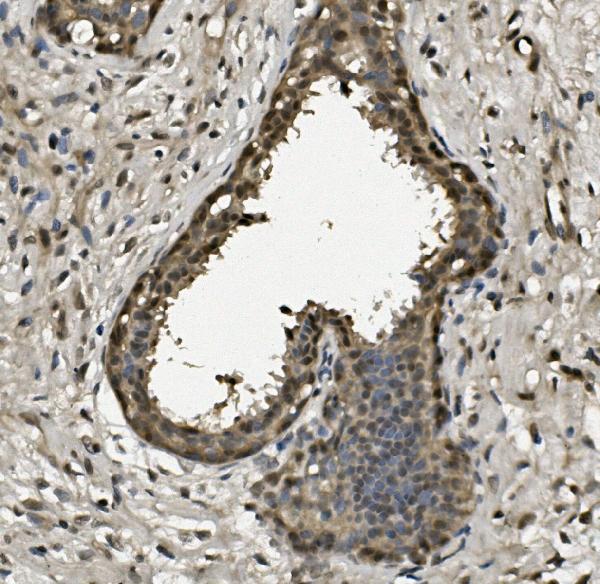

IHC (Immunohistochemisry)

(Figure 3. IHC analysis of RPA32/RPA2 using anti-RPA32/RPA2 antibody (AAA125632).RPA32/RPA2 was detected in paraffin-embedded section of human mammary cancer tissue. Heat mediated antigen retrieval was performed in EDTA buffer (pH8. 0, epitope retrieval solution). The tissue section was blocked with 10% goat serum. The tissue section was then incubated with 1μg/ml rabbit anti-RPA32/RPA2 Antibody (AAA125632) overnight at 4 degree C. Biotinylated goat anti-rabbit IgG was used as secondary antibody and incubated for 30 minutes at 37 degree C. The tissue section was developed using Strepavidin-Biotin-Complex (SABC) with DAB as the chromogen.)

IHC (Immunohiostchemistry)

(Figure 2. IHC analysis of RPA32/RPA2 using anti-RPA32/RPA2 antibody (AAA125632).RPA32/RPA2 was detected in paraffin-embedded section of human mammary cancer tissue. Heat mediated antigen retrieval was performed in EDTA buffer (pH8. 0, epitope retrieval solution). The tissue section was blocked with 10% goat serum. The tissue section was then incubated with 1μg/ml rabbit anti-RPA32/RPA2 Antibody (AAA125632) overnight at 4 degree C. Biotinylated goat anti-rabbit IgG was used as secondary antibody and incubated for 30 minutes at 37 degree C. The tissue section was developed using Strepavidin-Biotin-Complex (SABC) with DAB as the chromogen.)